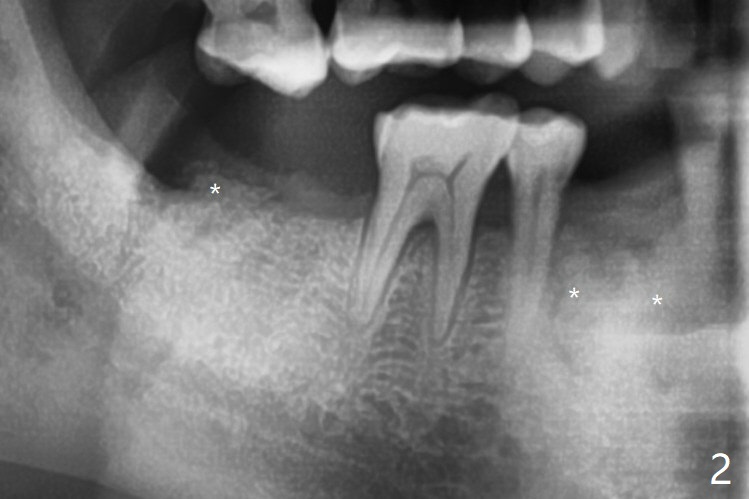

拔除32号牙时发现它接近31区(将要植牙),必须植骨(近中部分(远中塞入胶原塞)),27,28颊侧骨板缺失(大量肉芽组织),植骨理所应当,而且必须拼命推压,但愿推到颊侧骨板,细的皮质骨没有压制感,非要加入粗的松质骨皮质骨,一张12x12毫米胎盘膜剪成两片覆盖27/28和32拔牙窝,4-0 PGA缝线固定,拍摄术后半侧全景片后(图二 (*:骨粉)),使用牙周敷料保护伤口。27/28重叠,近远中8.11毫米,可以植入一个植体,做悬臂桥,或者植入两者之间。